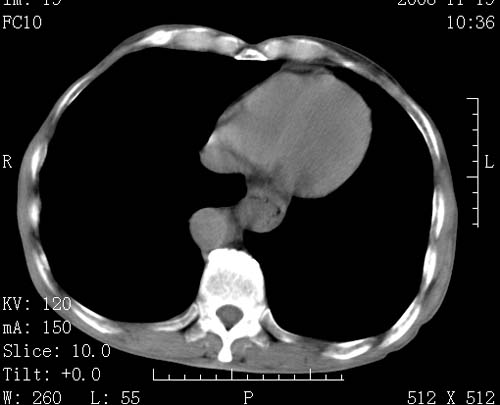

标题: CT16691:m 67 胃镜确诊食管下段及贲门癌 [打印本页]

标题: CT16691:m 67 胃镜确诊食管下段及贲门癌

术前查体,双肺部结节是转移?结核?请点评

转移 隆突下淋巴结亦肿大

首先考虑转移,纵隔内淋巴结亦肿大;

1)符合食管癌表现。2)两肺及纵隔淋巴结多发性转移瘤。3)左肺上叶舌段及两肺下叶炎症感染。

食管癌伴双肺转移,评述:肺部毛细血管网丰富,全身血液均快速流经肺部,癌细胞容易过滤定植,形成转移瘤,影象特点为以毛细血管末梢为中心的结节灶,边缘光滑锐利,少见有中心空洞着,不同来源的转移瘤可有各自特点,如甲状腺癌为双肺弥漫性微结节,本例有原发灶,双肺影象灶典型,左肺舌段条带状网格样伴胸膜天幕征,可视为癌性淋巴管炎。